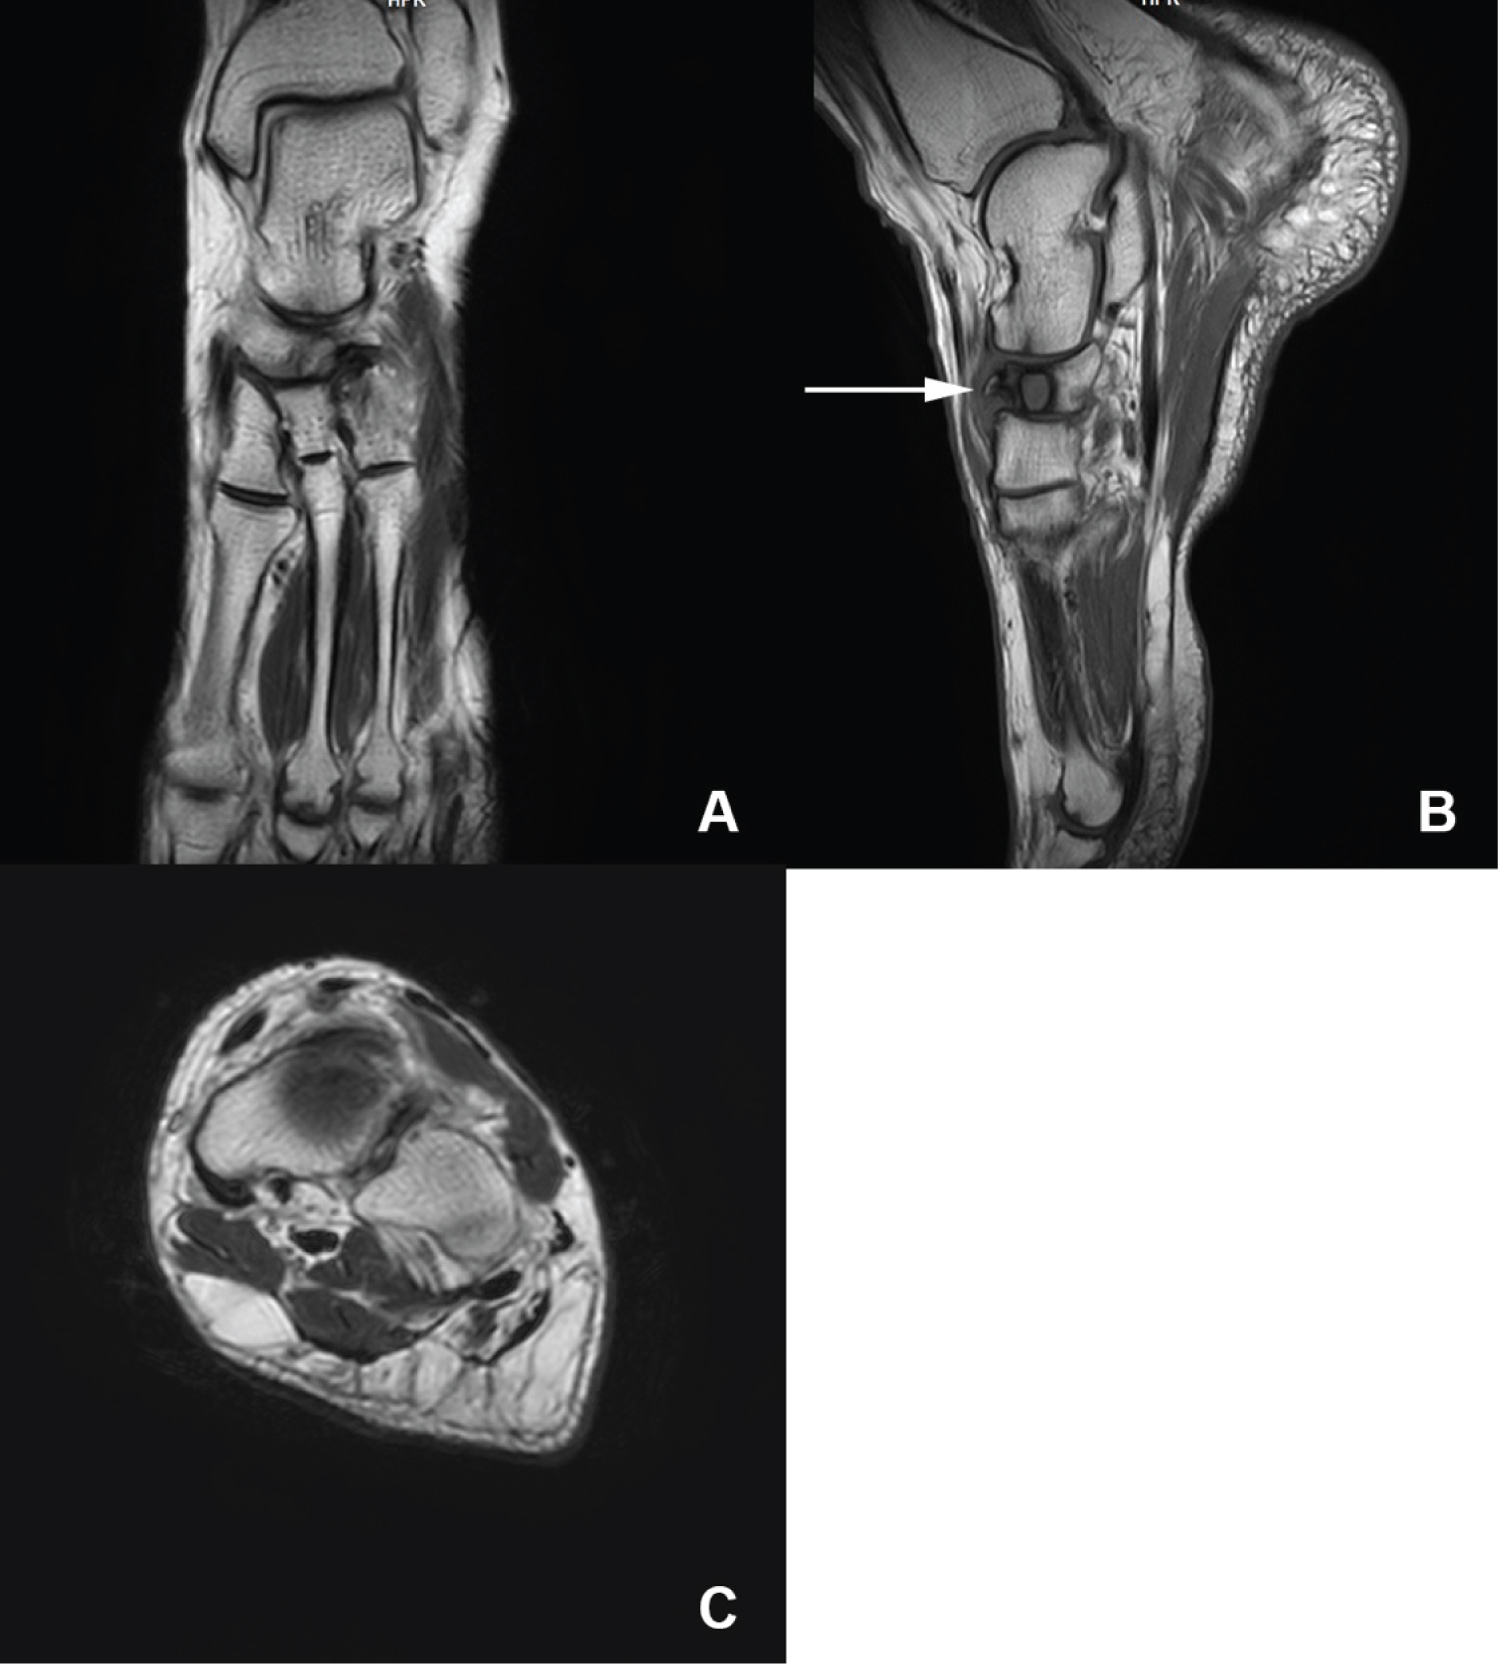

Because of the persistent pain, an MRI was performed, which showed bone marrow edema with low-signal areas on T1- and T2-weighted images in the marrow of the tarsal navicular bone, suggesting persistent osteonecrosis at the site of maximal pain (Figure 2).

Figure 2: MRI of the foot showing bone marrow edema as well as a cystic lesion of the tarsal navicular bone. View Figure 2